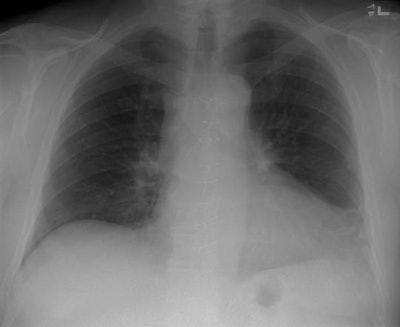

Below is the pre-discharge post-op frontal chest radiograph on a patient that had undergone median-sternotomy for coronary artery bypass grafting. The patient presented 3 weeks later with complaints of fever. A follow-up chest radiograph was performed and demonstrated no infiltrates, but a coned view of the sternal wires demonstrates migration of the 3rd sternal wire from the top- an early indication of mediastinitis. Unfortunately, this finding was not appreciated at the time the radiograph was performed and two days later the patient presented with complete sternal dehiscence.